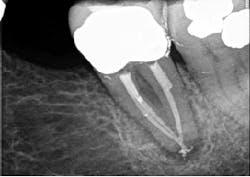

Figure 2 demonstrates a case with failing endodontic therapy. The mesial canals show inadequate obturation, and a periradicular radiolucent area is apparent. The tooth was retreated, and figure 3 shows the one-year follow-up. Note the resolution of the radiolucency. This case demonstrates the concept of removing the etiology of the bacteria with nonsurgical treatment.